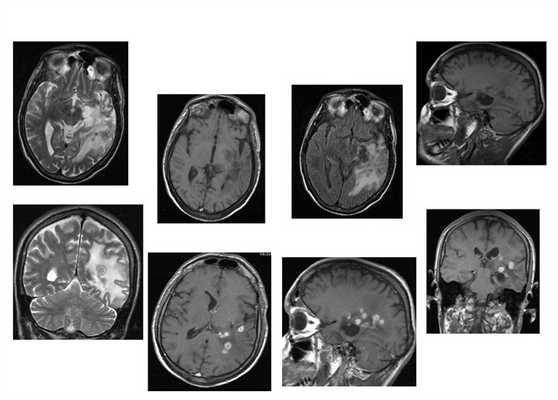

Токсоплазмоз у ВИЧ-инфицированного больного

МРТ в режиме Т2 (а,б) и Т1 с контрастированием (в-е) выявляет множественные очаговые изменения с накоплением контраста - симптом «мишени». В правом полушарии мозжечка образование по характеристиками похожее на абсцесс.

Пациент Н., 30 лет.

Динамика МРТ картины от 22.08.2008 к 12.11.2008![Поражение головного мозга при ВИЧ инфекции]()

Пациентка П.

Тяжелый токсоплазмоз+ВИЧ (летальный исход через 3 дня после исследования)Прогрессирующая мультифокальная лейкоэнцефалопатия